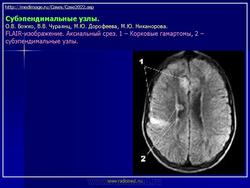

На поверхности мозга наблюдаются единичные или множественные глиома-тозные узлы, по цвету несколько светлее окружающего мозга и плотнее его на ошупь, возможна их кальцификация. Узлы могут быть и в белом веществе, под­корковых ганглиях, а также в стволе мозга и в мозжечке.

Встречаются и аномалии развития извилин мозга в виде микро- и пахигирии. Заболевание чаще носит спорадический характер. Бляшки достигают диаметра 5-20 мм. В коре больших полушарий и мозжечка иногда могут быть обнару­жены пластинчатые тельца, напоминающие амилоид. Происходит дегенерация клеток коры. При КТ-исследовании головы нередко можно выявить кальцифика-ты и глиальные узелки в паравентрикулярной области, субэпендимарно вдоль на­ружных стенок боковых желудочков, в зоне межжелудочкового отверстия Мон­ро, реже - в мозговой паренхиме. На М РТ головного мозга в 60% выявляются гипотеденсивные очаги в одной или обеих затылочных долях, которые расце­ниваются как участки неправильной миелинизации (Козлов А.В., 2002).